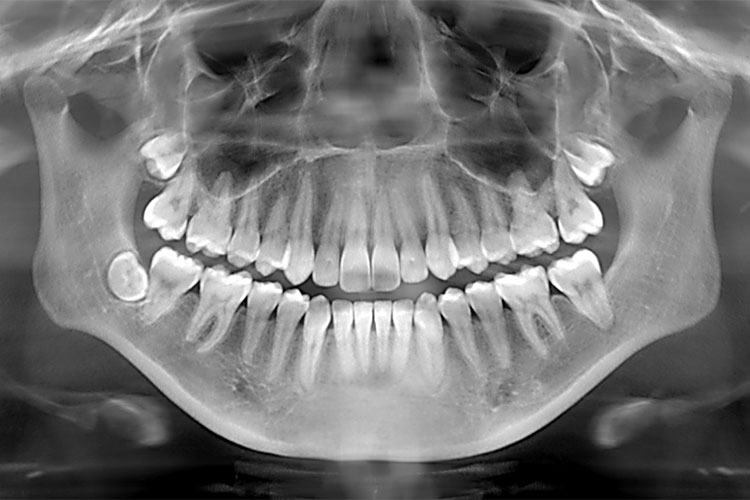

2.数据集准备与训练

本研究使用了包含口腔牙齿CT影像的数据集,并通过Labelimg标注工具对每张图像中的目标边框(Bounding Box)及其类别进行标注。然后主要基于YOLOv8n这种模型进行模型的训练,训练完成后对模型在验证集上的表现进行全面的性能评估及对比分析。模型训练和评估流程基本一致,包括:数据集准备、模型训练、模型评估。本次标注的目标类别为口腔牙齿CT影像,数据集中共计包含4647张图像,其中训练集占3684张,验证集占963张。部分图像如下图所示:

部分标注如下图所示: